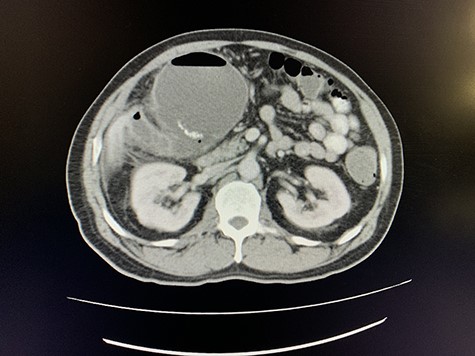

A size 12 French percutaneous catheter was inserted into the large liver abscess. The purulent material drained tested negative for organisms, amoebic and hydatid disease (Fig. 4). A sinogram was performed by injecting contrast through the catheter, showing passage into the ascending colon, confirming the initial diagnosis (Fig. 5).

Axial view of arterial phase of CT scan of the abdomen cholecystitis with pneumobilia with resolving liver abscesses with percutaneous pigtail catheter in situ.